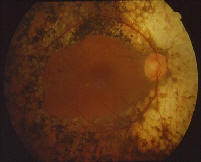

QU'EST-CE QUE LA RETINOPATHIE DIABETIQUE ?

La rétinopathie diabétique (= RD) est l'atteinte micro-circulatoire liée au diabète.

Elle peut être responsable de cécité d'autant qu'elle passe longtemps inaperçue car asymptomatique : une fois installée, elle est irréversible.

Son MEILLEUR traitement consiste en un équilibre PARFAIT de la glycémie et de la tension artérielle, les traitements laser ou chirurgicaux

(vitrectomies ou injections intra-vitréennes) n'étant là que pour retarder ou stabiliser son évolution.

Traitement laser (flèche)